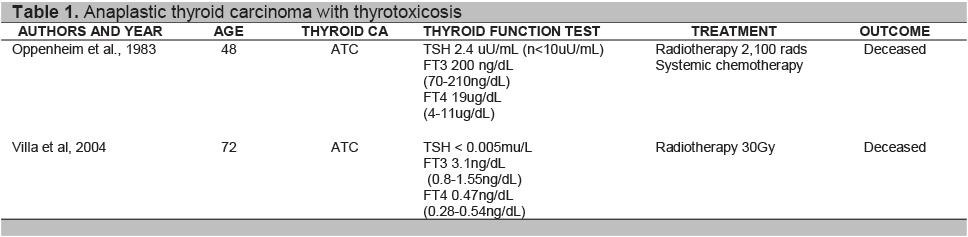

Click here to download Table 1

Table 1. Anaplastic thyroid carcinoma with thyrotoxicosis

Anaplastic cells do not express thyroid specific genes and thyroid function test are usually normal.9 Sung and Cavalieri explained that hyperthyroidism with thyroid carcinoma include those which produce thyroid hormone autonomously, and causes destructive thyrotoxicosis by rapid cancerous invasion of the normal thyroid tissue. 10,16 Review of literature showed case reports of destructive thyrotoxicosis resulting from the malignant process 8,10 as seen in Table 1. Oppenheim et al.(1983) reported a 48-year-old man with anaplastic thyroid cancer (small cell type) presenting initially with destructive thyrotoxicosis and hypothyroidism.8 Villa et al (2004) reported a 76-year-old female diagnosed with Wegener’s granulomatosis who presented with thyrotoxicosis in a previously euthyroid multinodular goiter. Histopathological report showed ATC.10 Only one report cited ATC with Toxic multinodular goiter.15 Schlumberger9 stated that over a third of patients with ATC have long standing goiter, while Patel4 et al suggested presence of a thyroid tumor may dedifferentiate to ATC. Point mutation in the genes have been identified as an initiating event that lead to transformation of well differentiated thyroid carcinoma to poorly differentiated and anaplastic thyroid carcinoma. One explanation can be due to prolonged stimulation by TSH may be responsible for the transformation into undifferentiated thyroid carcinoma,9 though the frequency is rare, since anaplastic thyroid carcinoma represents a small number of percentage of thyroid carcinomas. 5,8 The presence of lymphocytic thyroiditis in our patient with an enlarged thyroid gland may represent chronic autoimmune thyroiditis. Autoimmunity may well coexist with a multinodular goiter and occurs in 10% of the population with goiter.